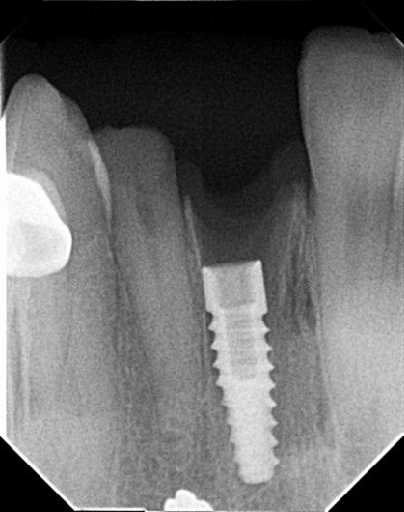

La radiografía periapical es una técnica de imagen intraoral utilizada en odontología para obtener una visualización detallada de un diente o implante y su entorno inmediato.

Este tipo de radiografía permite observar:

Gracias a su alta definición, es una prueba imprescindible tanto para el diagnóstico como para el seguimiento de tratamientos implantológicos.

Consiste en colocar el sensor radiográfico paralelo al eje longitudinal del diente o implante, mientras que el haz de rayos X incide perpendicularmente sobre ambos.

Es la técnica de elección para la identificación de implantes.